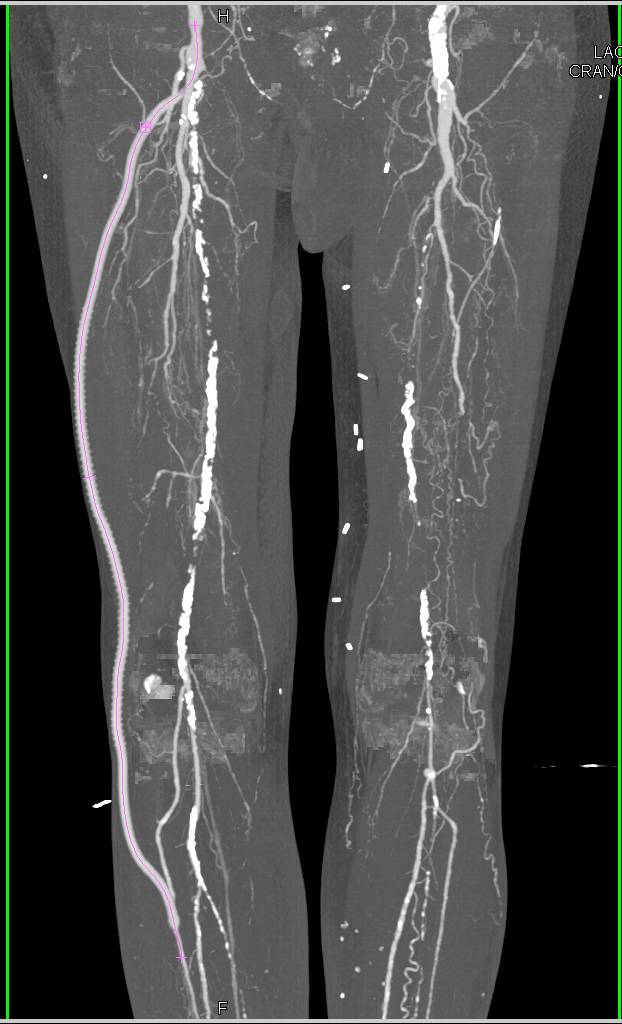

Femur Fracture with Bleed S/P GSW to Thigh